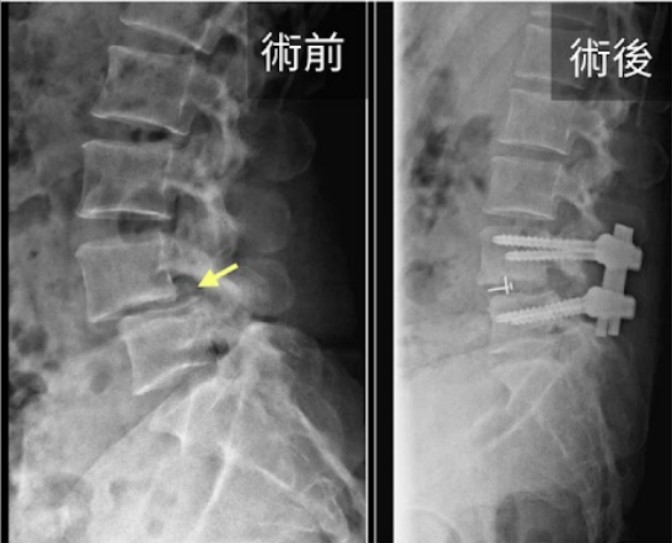

脊椎滑脫示意圖

椎體向前滑動造成椎間孔變窄與神經壓迫(示意圖)

• 內視鏡微創融合術 :利用微創技術進行神經減壓並置入植入物(釘子與支架),恢復脊椎高度與穩定度。

若以神經壓迫合併不穩定為主,常需「減壓 + 融合」以同時改善症狀並穩定節段。